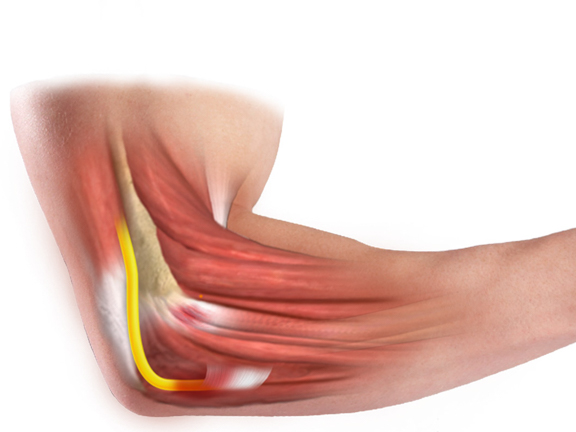

Анатомия локтевого сустава

Локтевой сустав относится к группе сложных, поскольку объединяет сразу три сочленения трёх разных костей: лучевой, локтевой и плечевой. Именно поэтому анатомия локтевого сустава человека невероятно сложна, ведь её следует рассматривать в контексте трёх разных суставов, объединённых одной суставной сумкой.